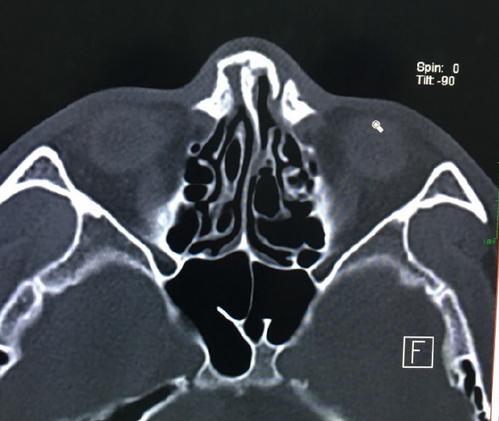

事实上,早在去年与播求的一番战,一龙就是带伤作战,而且那场比赛他表现更好,更应该获胜。赛后,他在微博上台上晒出了自己赛前的CT检查报告,证明自己是带伤作战。

他写道:“赛前一个多月训练鼻骨多处骨折,医生说伤筋动骨一百天不能碰。当时是非常非常难过的,因为难能可贵的世纪之战来之不易。就这样不能有任何改变继续训练,更可惜的是在赛前10多天实战训练时不小心胸骨又被撞骨裂(抗击打也明显减弱)三次鼻子被碰到、骨折严重停止训练实战……”